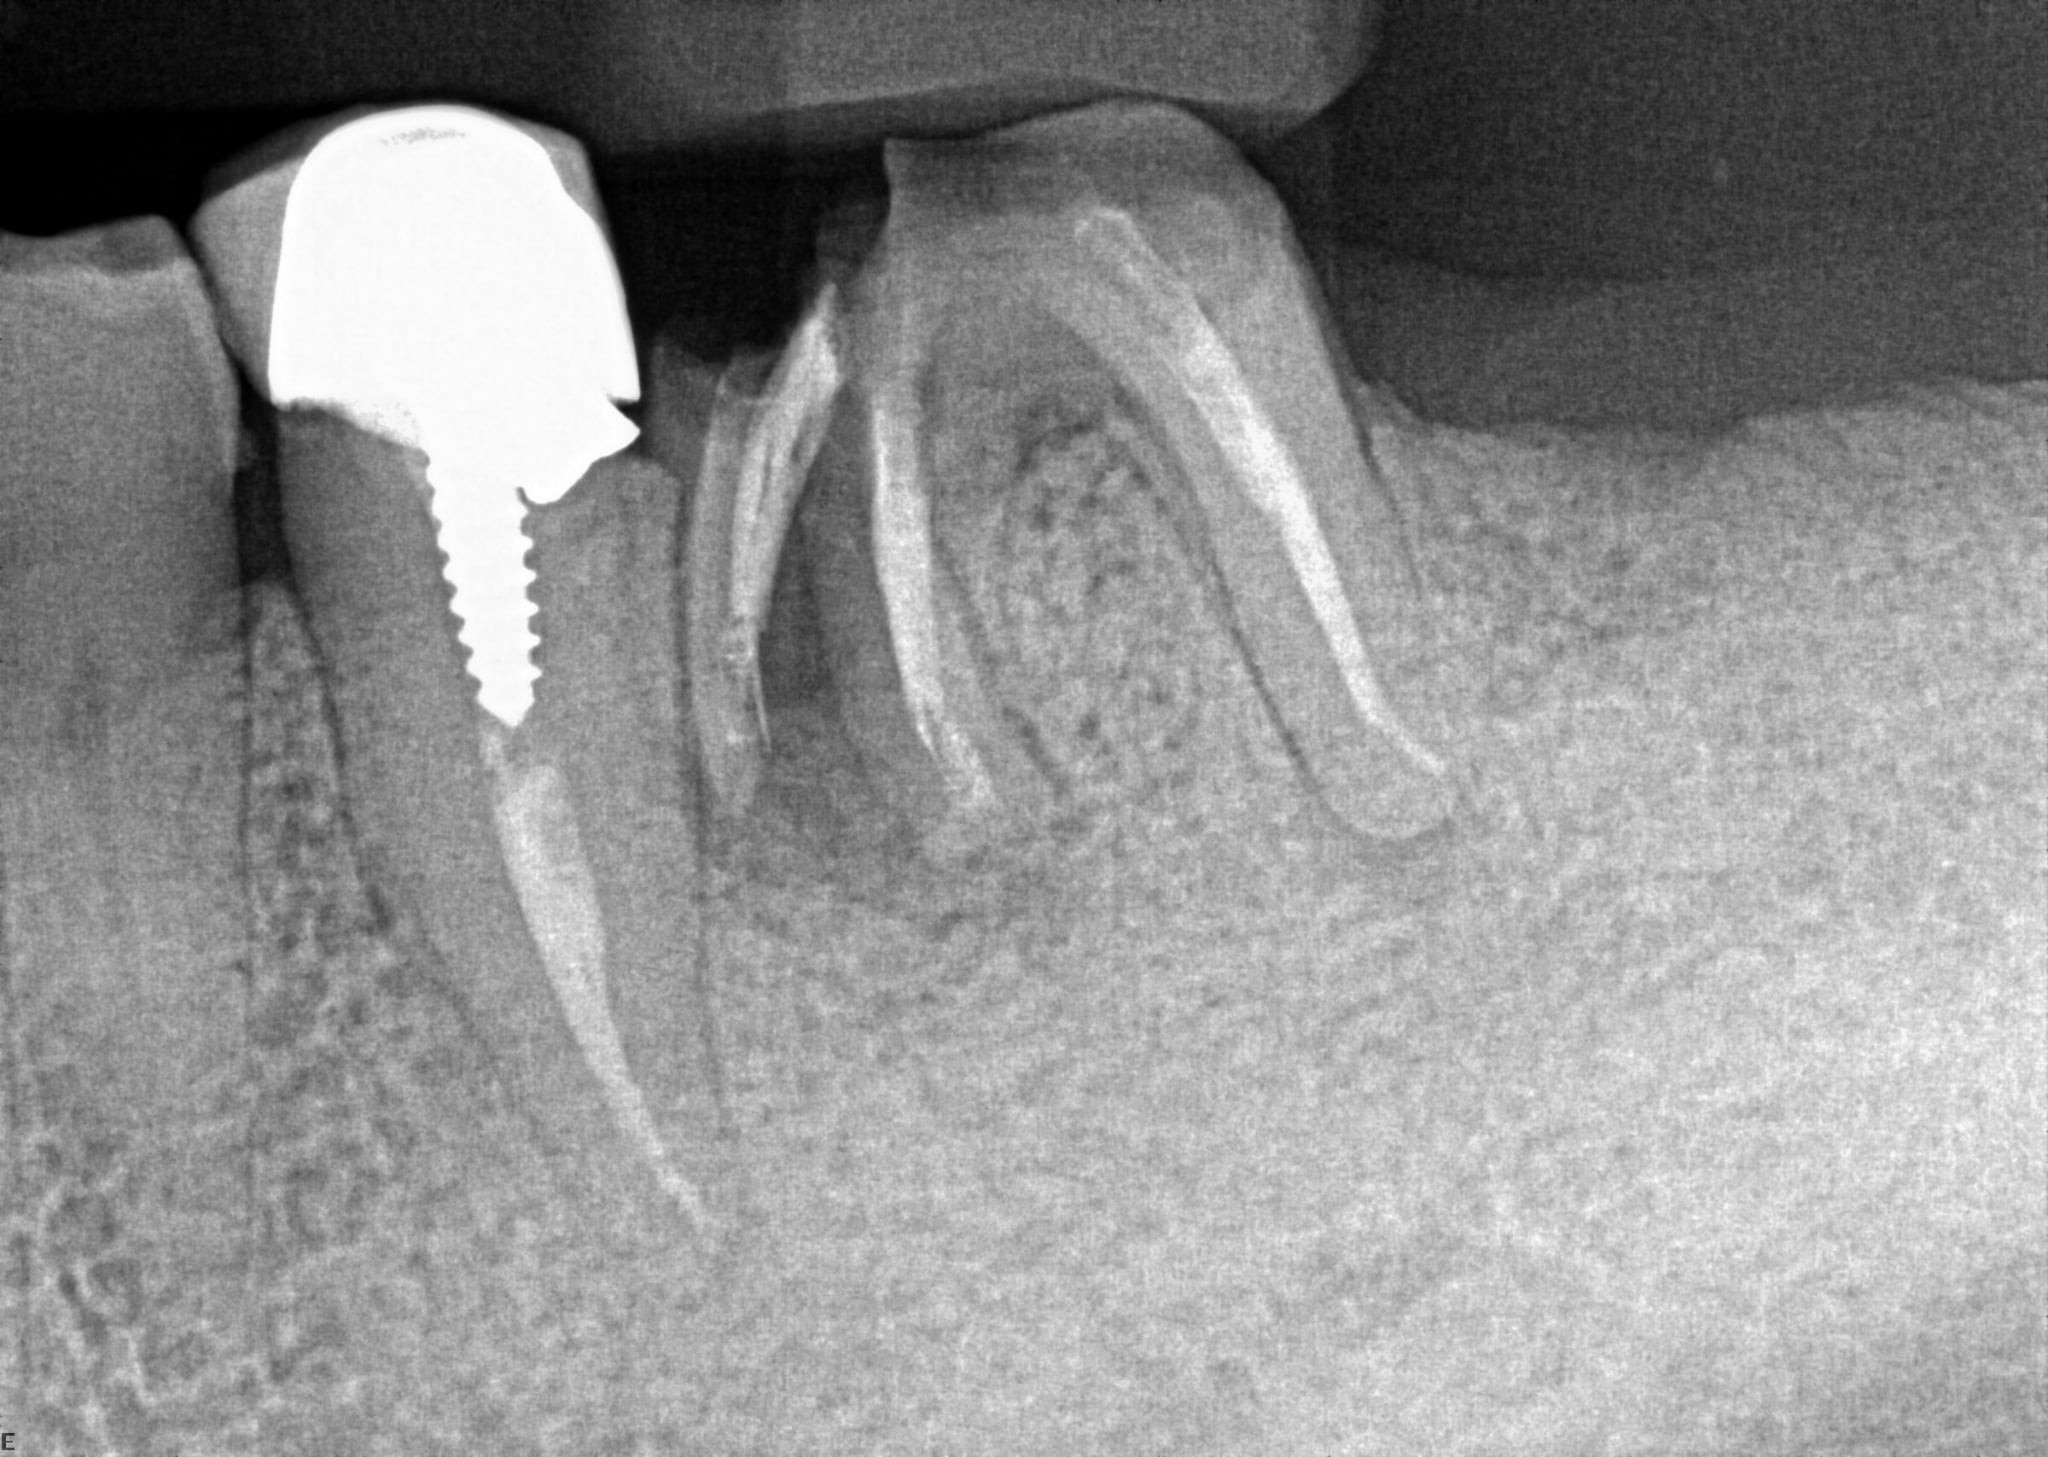

4. What option can describe the post placement in the X ray bellow for the tooth # 3.6?